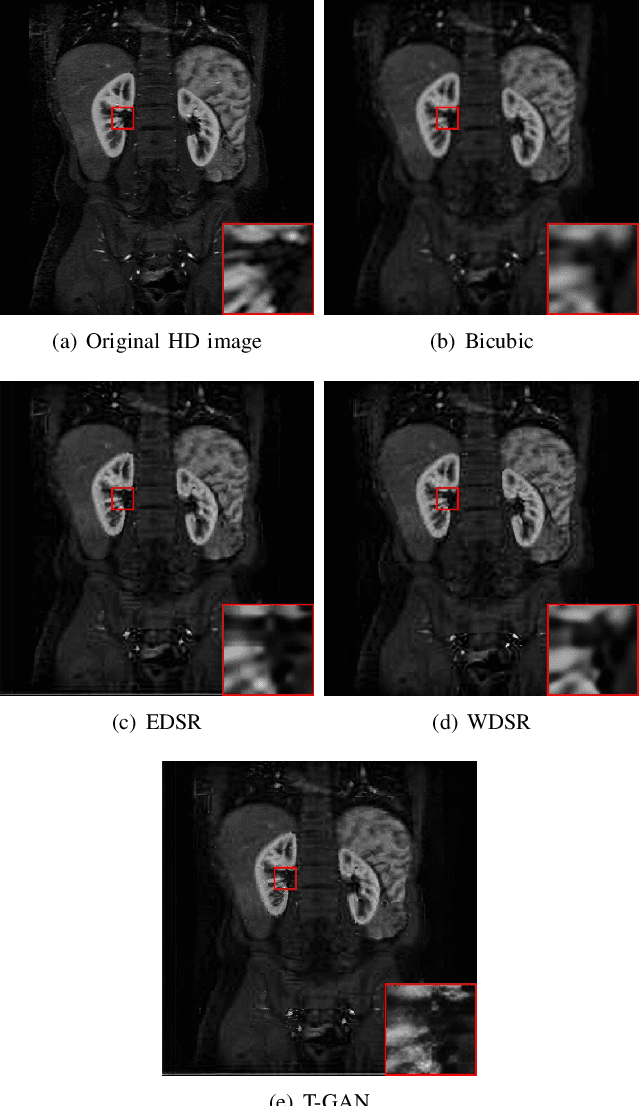

Abstract:Because of the necessity to obtain high-quality images with minimal radiation doses, such as in low-field magnetic resonance imaging, super-resolution reconstruction in medical imaging has become more popular (MRI). However, due to the complexity and high aesthetic requirements of medical imaging, image super-resolution reconstruction remains a difficult challenge. In this paper, we offer a deep learning-based strategy for reconstructing medical images from low resolutions utilizing Transformer and Generative Adversarial Networks (T-GAN). The integrated system can extract more precise texture information and focus more on important locations through global image matching after successfully inserting Transformer into the generative adversarial network for picture reconstruction. Furthermore, we weighted the combination of content loss, adversarial loss, and adversarial feature loss as the final multi-task loss function during the training of our proposed model T-GAN. In comparison to established measures like PSNR and SSIM, our suggested T-GAN achieves optimal performance and recovers more texture features in super-resolution reconstruction of MRI scanned images of the knees and belly.